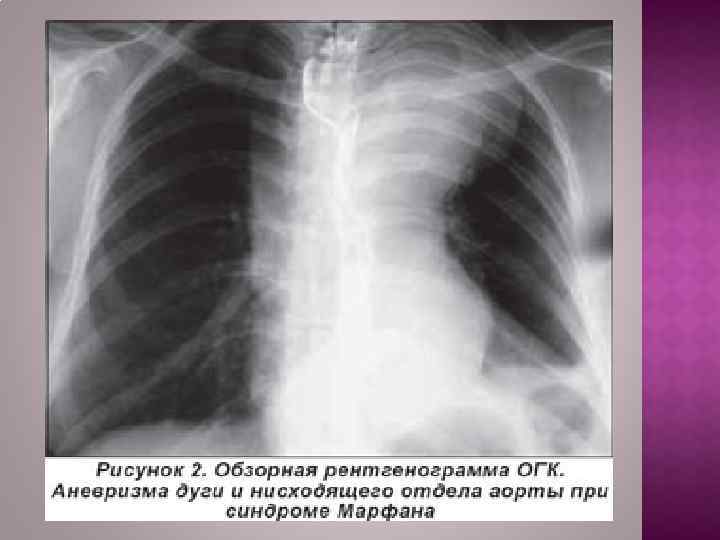

При осмотре больных с небольшими аневризмами внешние признаки заболевания отсутствуют. При больших аневризмах корня аорты и восходящего ее отдела с компрессией верхней полой вены и правых отделов сердца выявляют одутловатость, цианоз лица и шеи, набухание шейных вен вследствие затруднения венозного оттока. Больные, страдающие синдромом Марфана, в основе которого лежит аномалия развития соединительной ткани, имеют характерный внешний вид: высокий рост, непропорционально длинные конечности и паукообразные пальцы, кифосколиоз, воронкообразную грудную клетку; в 50% случаев имеется вывих или подвывих хрусталика. У больных , страдающих острыми инфекционными заболеваниями (сифилис) или у больных с аневризмой достигающей размеров больше 6 см изменяется форма грудной клетки У больных с расслоением дуги аорты и брахиоцефальных артерий наблюдают асимметрию пульса и давления на верхних конечностях. При перкуссии нередко определяется расширение границ сосудистого пучка вправо от грудины. Частым симптомом заболевания является систолический шум, который при аневризмах восходящей аорты и дуги аорты выслушивается во втором межреберье справа от грудины. Он обусловлен турбулентным характером кровотока в полости аневризматического мешка и дрожанием отслоенной интимы-мембраны. При аневризме, сочетающейся с недостаточностью аортального клапана, в третьем межреберье слева от грудины выслушивается диастолический шум.

Рентгенологическим признаком аневризмы грудной аорты является наличие гомогенного образования с ровными четкими контурами, не отделимого от тени аорты и пульсирующего синхронно с ней. Трансторакальная эхокардиоаортография дает возможность выявить аневризмы восходящего отдела и дуги аорты, определить их размеры, наличие фенестрации интимы и расслоения аорты, аортальной регургитации. Чреспищеводная эхокардиоаортография позволяет еще лучше распознать патологию аортального клапана, синусов Вальсальвы, устий коронарных артерий, тубулярной части восходящей аорты, а главное — диагностировать расслоение аорты с выявлением внутренней мембраны и проксимальной фенестрации. Компьютерная томография и магнитно-резонансная ангиография позволяют определить локализацию и размеры аневризмы, наличие расслоения аорты и внутрианевризматического тромба, дать характеристику стенки аорты. Рентгеноконтрастная аортография по-прежнему является «золотым стандартом» в диагностике аневризм аорты. При грудных и особенно расслаивающих аневризмах необходимо выполнять контрастирование всей аорты (панаортография) с определением локализации аневризмы, взаимоотношения ее с магистральными ветвями, наличия фенестрации и расслоения.